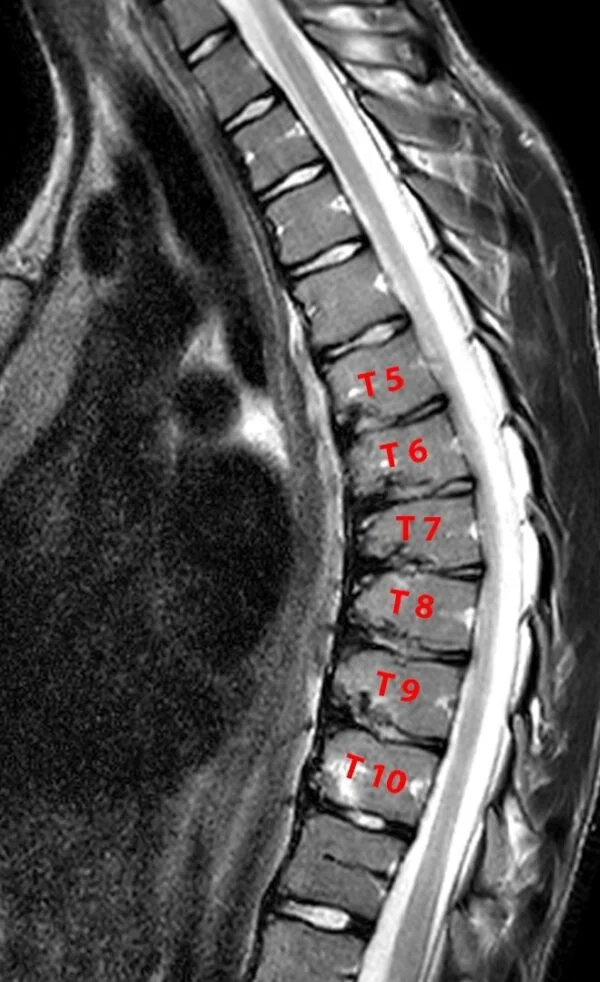

It is caused by abnormal development of the bones and/ or ligaments of the spine. This leads to wedging of the spinal bones [“vertebrae”].

Pain is the hallmark of this disease. In addition, sometimes, patients can develop a hunchback deformity of the back. This problem is noted only if the disease affects the upper or mid back region and is extremely rare in afflictions of the lower back. Rarely, a severe hunchback deformity can affect the spinal cord function leading to weakness in the lower limbs or clumsiness while walking. This is again most commonly noted in afflictions of the mid back rather than upper back regions.